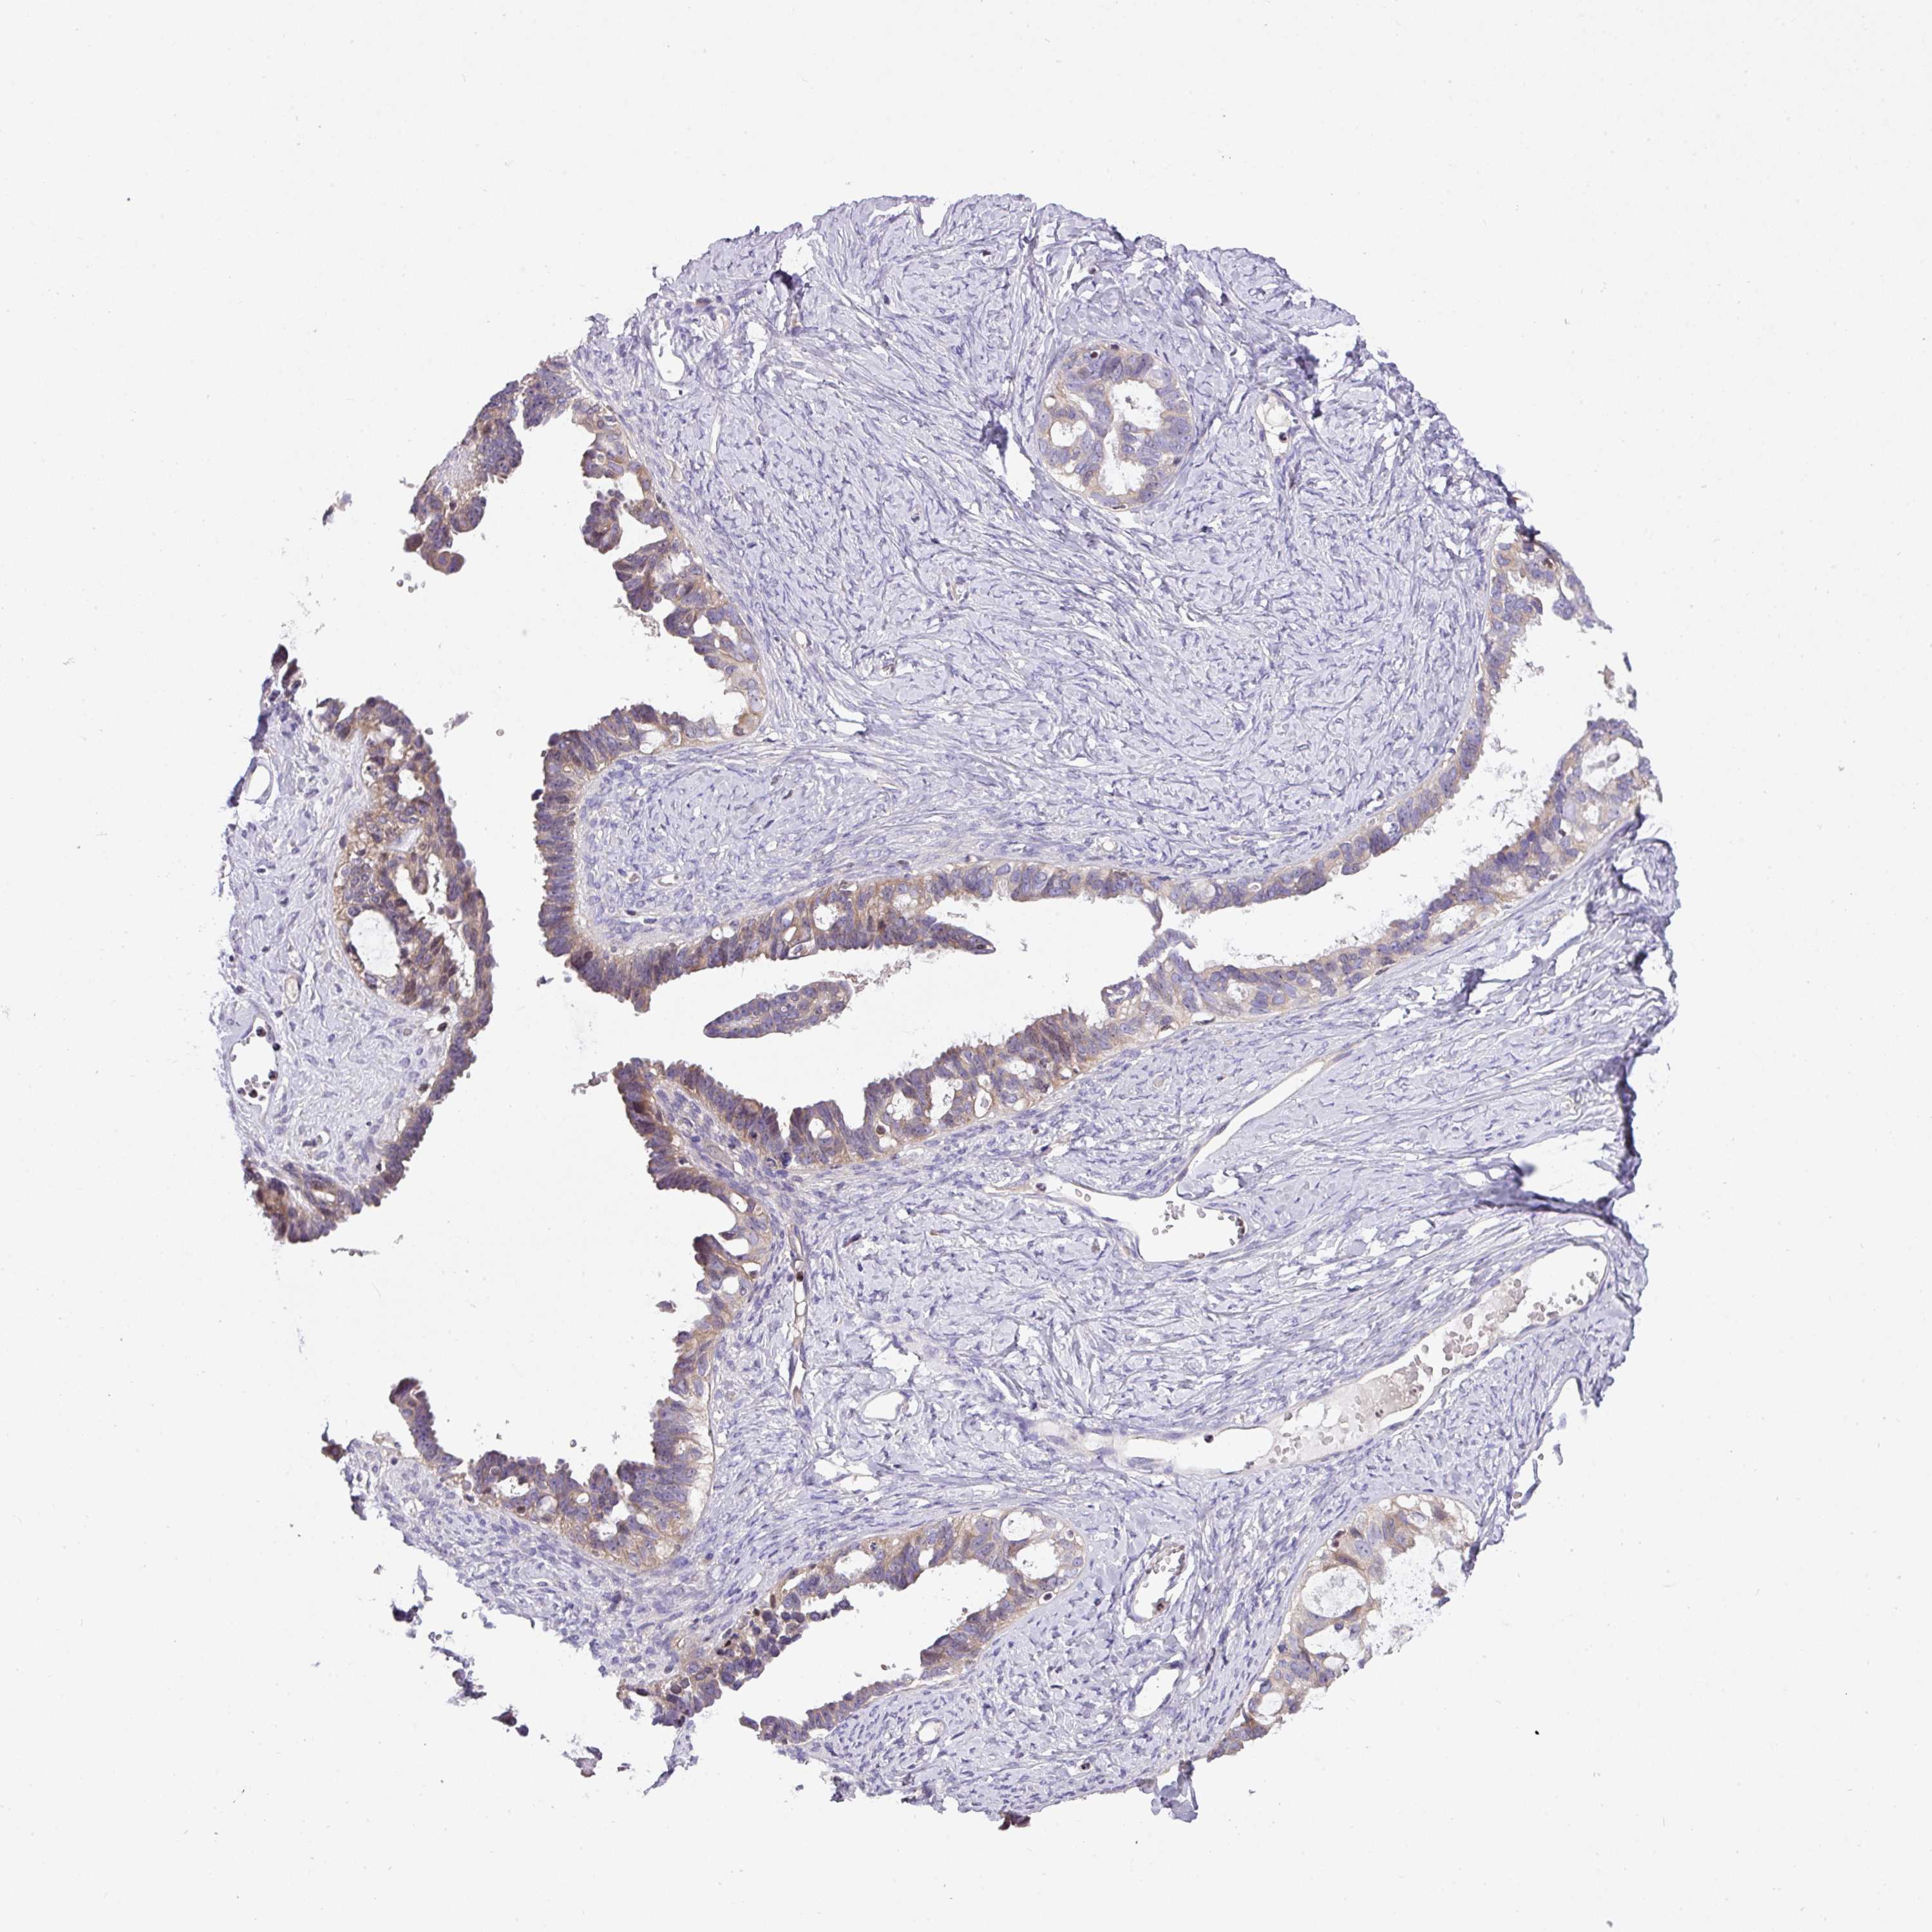

OVARIAN CANCER - Protein expressioni

A mouse-over function shows sample information and annotation data. Click on an image to view it in a full screen mode. Samples can be filtered based on level of antibody staining by selecting one or several of the following categories: high, medium, low and not detected. The assay and annotation is described here.

Note that samples used for immunohistochemistry by the Human Protein Atlas do not correspond to samples in the TCGA dataset.

Antibody stainingi

Antibody staining in the annotated cell types in the current human tissue is reported as not detected, low, medium, or high, based on conventional immunohistochemistry profiling in selected tissues. This score is based on the combination of the staining intensity and fraction of stained cells.

Each image is clickable and will lead to virtual microscopy that enables deeper exploration of all samples and also displays staining intensity scores, fraction scores and subcellular localization as well as patient and tissue information for each sample.

Antibody HPA054639

Adenocarcinoma, NOS

Carcinoma, endometroid

Cystadenocarcinoma, serous, NOS